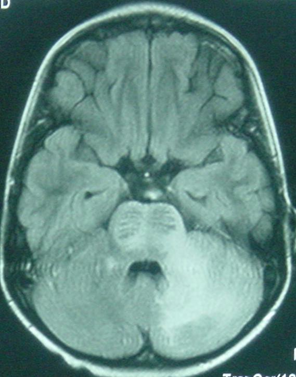

Progressive multifocal leukoencephalopathy (PML) is a demyelinating disease of the central nervous system that results from infection with JC virus (JCV), a neurotropic polyomavirus. Asymptomatic primary infection with JC virus occurs in childhood and antibodies can be found in 86% of adults. JCV remains latent in kidneys and lymphoid organs, but, in the context of profound immunosuppression as occurs in HIV infection, JCV can reactivate, spread to the brain, and induce a lytic infection of oligodendrocytes, the CNS myelin-producing cells. PML is relatively uncommon among children. Median age at HIV-associated PML diagnosis was 12 years in one review.

Clinical features: Paresis, speech abnormalities, gait disturbances, ataxia, cranial nerve palsies and seizures. CSF white cell count, protein and glucose are usually normal to slightly elevated in patients with PML.

On cranial CT, PML lesions may appear as hypodense patchy or confluent white matter regions. Typical MRI features include single or multiple non-enhancing, non-space-occupying, predominantly white matter lesions commonly involving the frontal and parieto-occipital subcortical white matter.

Definitive diagnosis of PML can be established by detection of JCV DNA in the CSF or viral proteins on brain biopsy. Sensitivity of JCV DNA CSF PCR is as low as 59% but the specificity is about 100%.